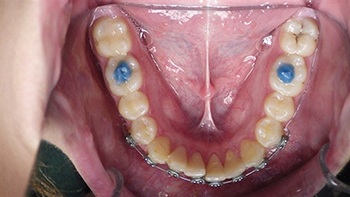

Figs. 7-8: Two-week follow-up with continued improvement in positioning and stabilization.

Over the following weeks, the orthodontic approach proved successful. Within a week, the extruded incisors showed visible improvement in position, and by two weeks, they were nearly realigned. The orthodontist planned to maintain the light archwire for several more weeks before replacing it with a bonded 3–3 retainer for long-term stabilization (Figs 3–8).

Throughout the short-term follow-up, the teeth remained firm and asymptomatic. The gingival and periodontal tissues appeared stable, with no signs of acute infection. Nevertheless, the community emphasized that this positive early response did not eliminate the need for long-term vigilance. Regular radiographs and ongoing monitoring by both the general dentist and an endodontist were considered essential.